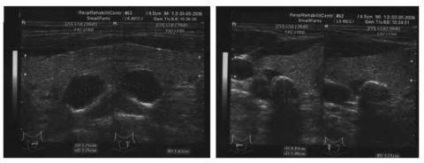

Mellékpajzsmirigy ultrahanggal

A normális állapotban, ezek az endokrin szervek ultrahang jelennek homogén hypoechoic ovális vagy lekerekített sima képződése szempontjából tiszta kontúrokkal, bármilyen mennyiségben legfeljebb 30 mm, amelyek vannak elhelyezve a felső és alsó pólusa a pajzsmirigy hátsó fal. Erezettség mellékpajzsmirigy a legtöbb esetben hiányzik.

Meghatározása egy ultrahangos belső áramlási csak akkor lehetséges, növeli a test mérete (32% az esetek másodlagos paraméterek 21H10 milliméter).

Annak érdekében, hogy meghatározzuk, mekkora mennyiség változott mellékpajzsmirigy szöveteinek, a következő képletet: V mellékpajzsmirigy (cm3) = π / 6hAhBhC, ahol A, B és C - a test méreteinek hüvelykben. Ha glandulae parathyroideae térfogata akár 0,5 cm3, ők tekinthetők, hogy kicsi, és ha több, mint 0,5 cm3, majd - nagy.

A gyakorlatban az ultrahang szakemberek a felmérés a mellékpajzsmirigyei meglehetősen gyakori álnegatív és álpozitív eredmények hasonlósága miatt a megnövekedett glandulae parathyroideae csomós daganatok a pajzsmirigy, található a megfelelő helyeken:

- Adenoma (lásd mellékpajzsmirigy adenoma -. Etiológiája, klinikai kezelés és prognózis).

- Kolloid cysta.

- Multinoduláris golyva.